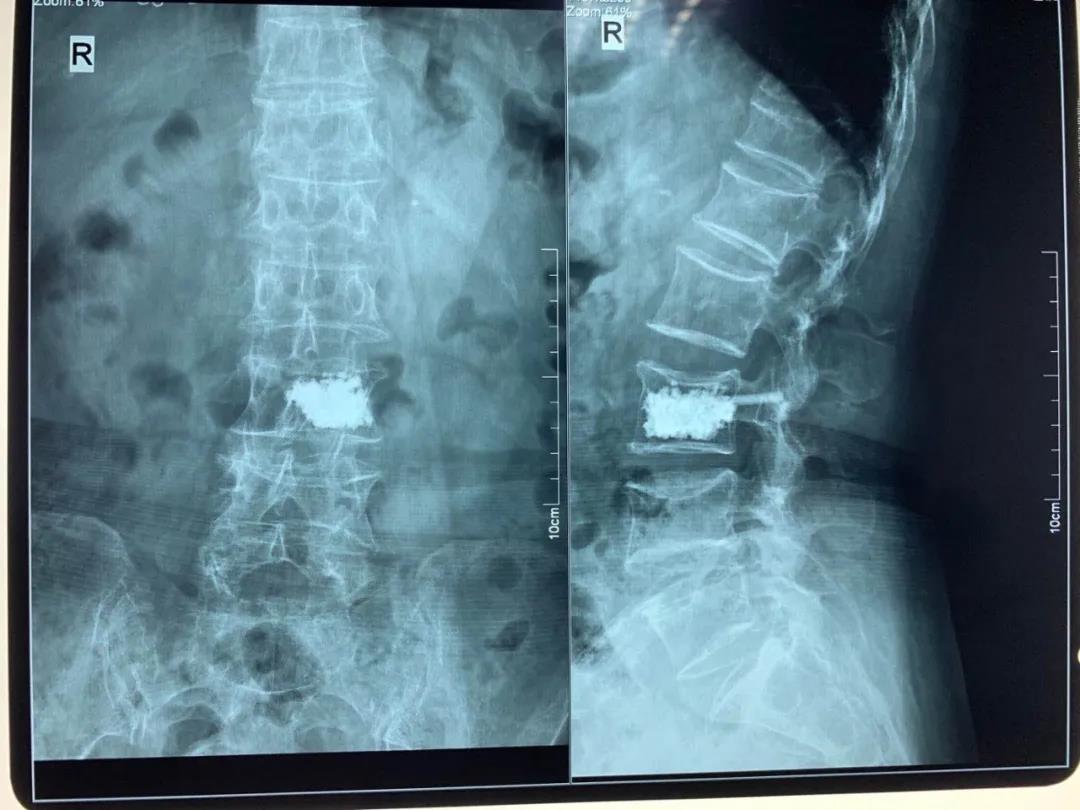

椎體骨折

青壯年椎體骨折無神經壓迫癥狀骨二科采用微創(chuàng)經皮椎弓根螺釘內固定術,避免了手術大切口引起的椎旁肌破壞,老年骨質疏松性椎體壓縮骨折骨二科采用局麻下經皮椎體成形術(PVP、PKP)術,術后患者即可解除疼痛,第二天恢復正常生活。

pvp